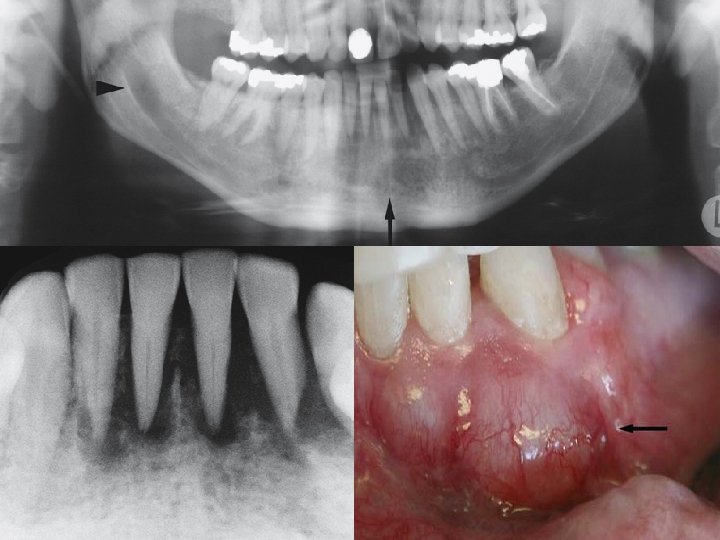

Clinical photograph shows leukoplakia that transformed to gingival cancer Intraoral panoramic view shows diffuse bone destruction